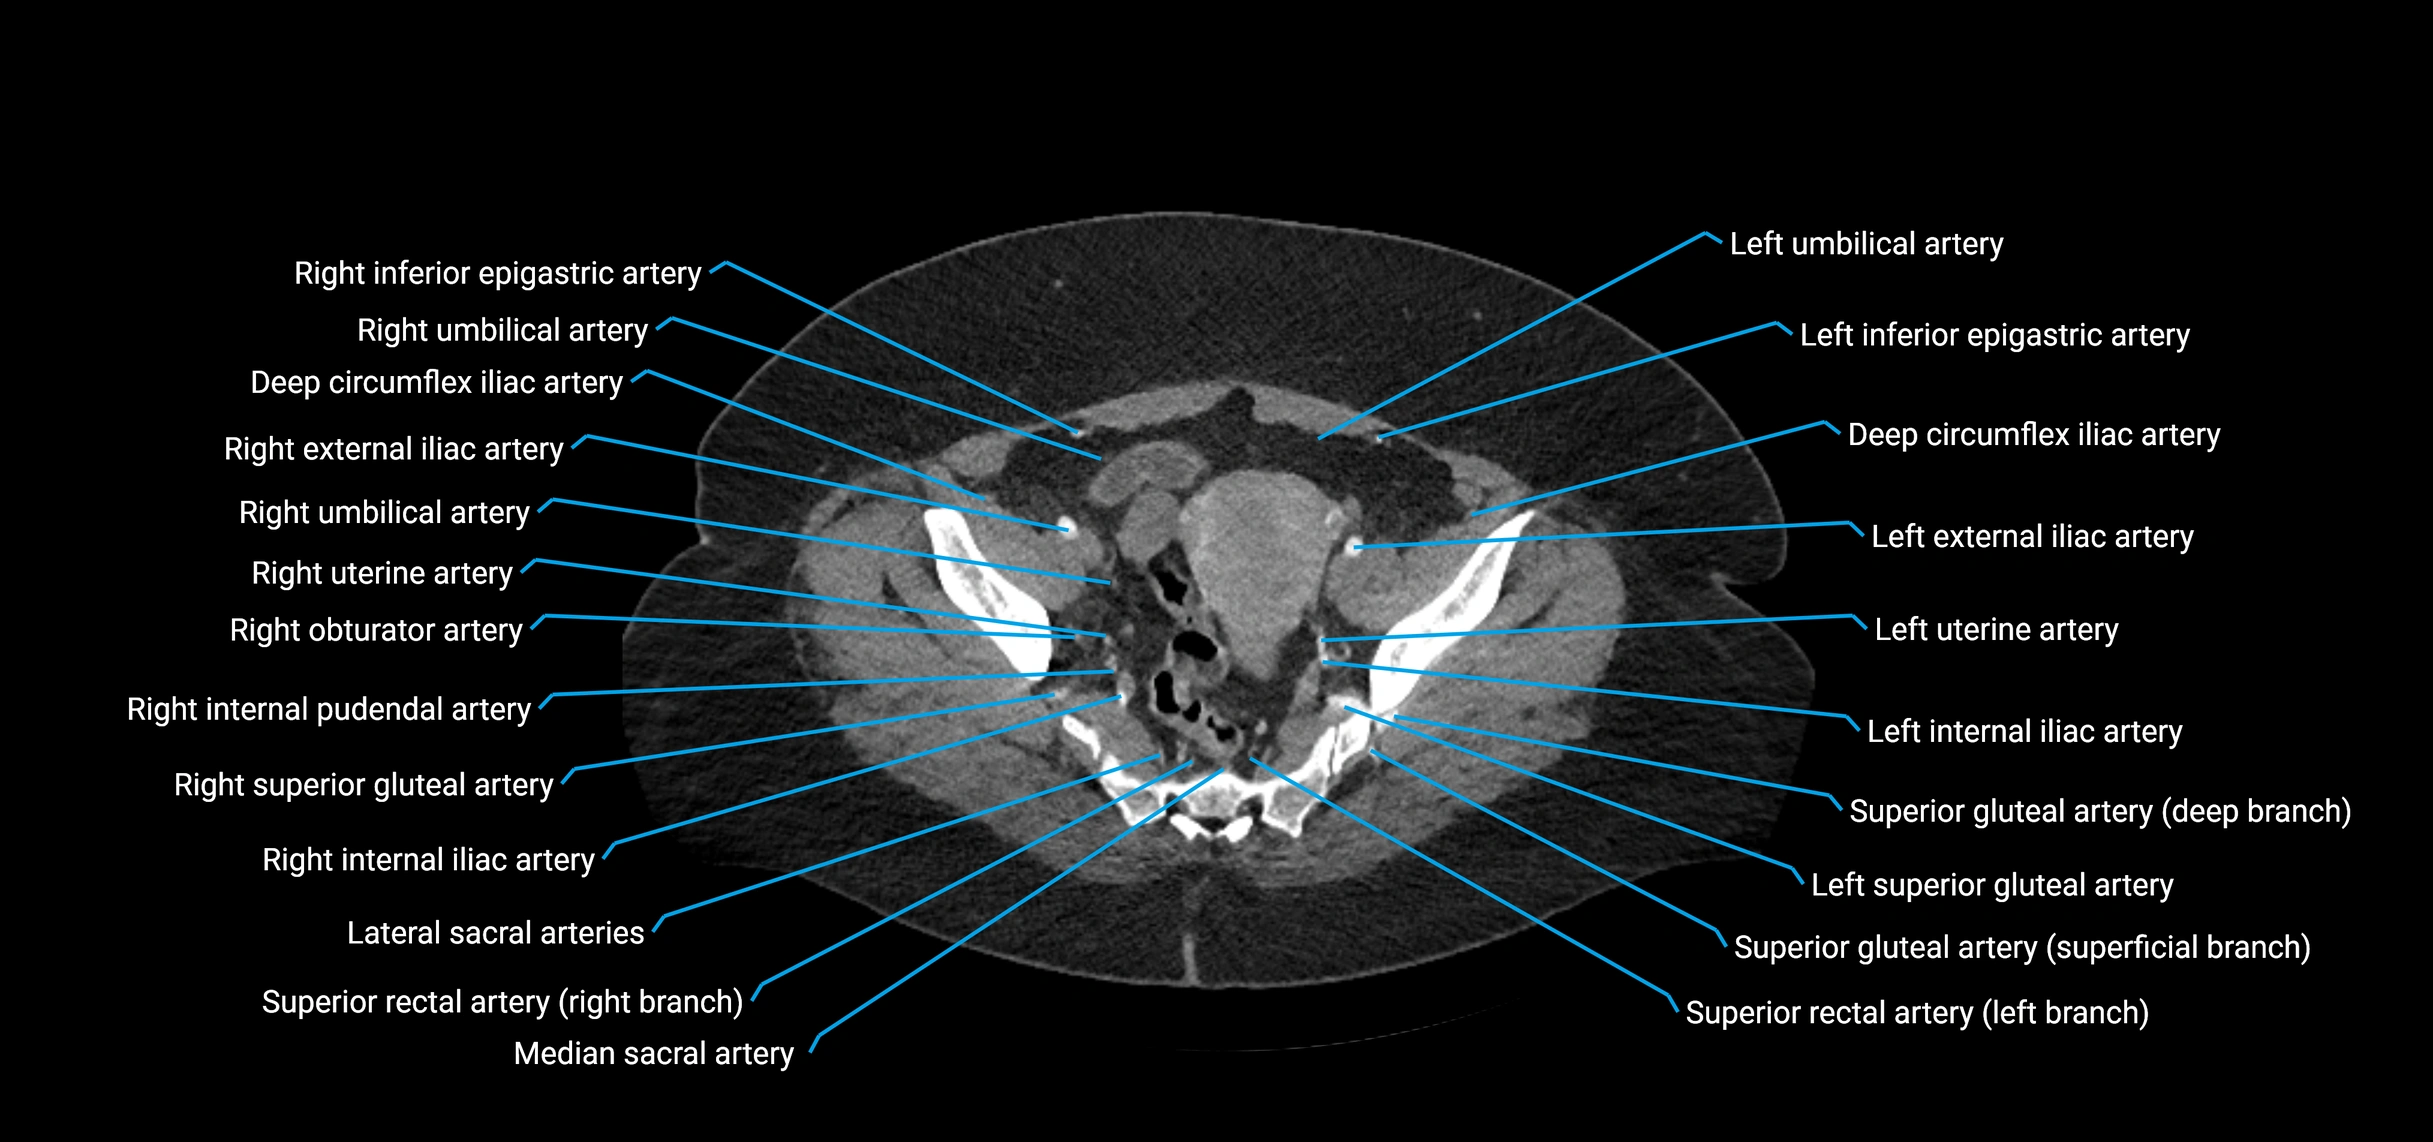

Contrast-enhanced CT (CTA):

• Gold standard for abdominal aortic imaging

• Provides excellent detail of lumen, wall, aneurysm, thrombus, and branch vessels

• Multiplanar and 3D reconstructions help in aneurysm measurement, stent graft planning, and dissection evaluation

• Detects acute rupture, traumatic injury, or occlusion with high sensitivity